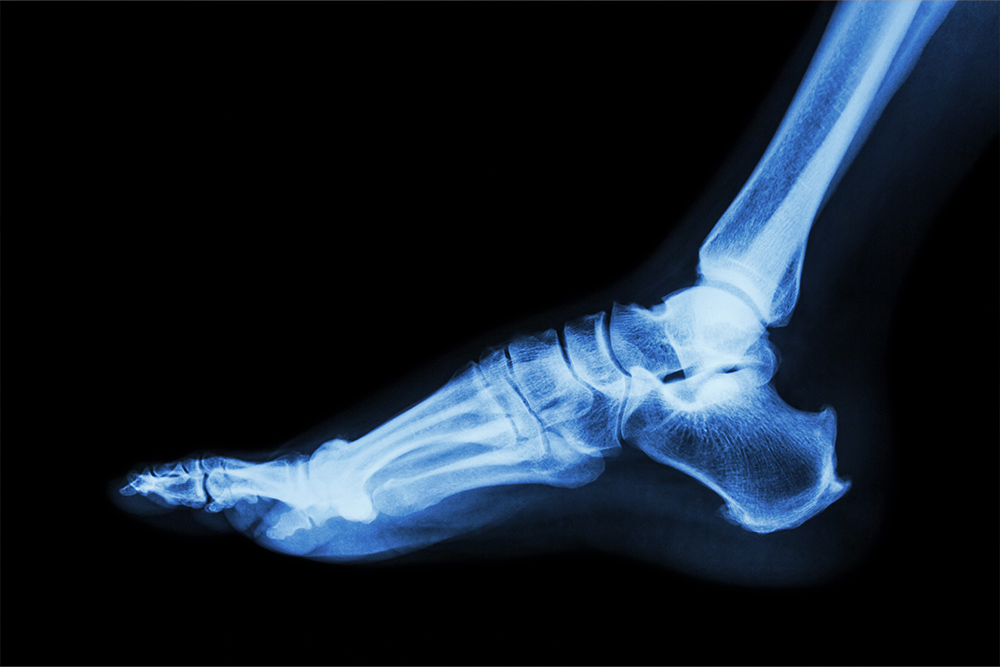

When pain, swelling, or injury occurs in your foot, ankle, or lower leg, an X-ray is often the first step in diagnosis. This quick and painless imaging test helps your doctor visualize the internal structure of your bones and joints to determine the cause of discomfort or detect possible damage.

X-rays use a small amount of low-level radiation to create detailed images of the body’s internal structure. Dense materials like bones appear white on the image, revealing fractures, alignment issues, or growths.